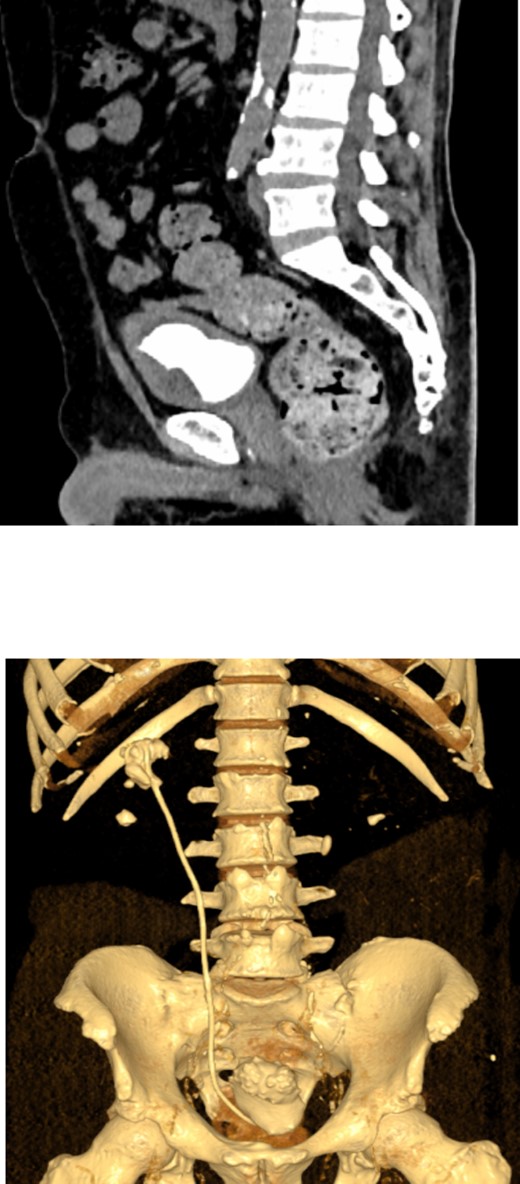

On physical examination, he had normal vital signs, no fever, and exhibited mild tenderness in the suprapubic area and right costovertebral angle. The results of the laboratory tests were normal, and the serum creatinine level was 0.8 mg/dl. Urine culture was negative for bacteria. Preoperative abdominal and pelvic ultrasound revealed two right renal stones, one measuring 4 cm in the upper pole and 2 cm in the lower pole with mild hydronephrosis, along with a large bladder stone measuring 6 cm, and a shadow of a double J stent. A computed tomography (CT) scan confirmed the presence of a 4 cm upper pole renal stone, a 1.8 cm lower pole renal stone, significant proximal pigtail calcification with mild hydronephrosis (Fig. 1A and B), and a 6 cm bladder stone deeply embedded in the distal pigtail (Fig. 2A and B). Additionally, small intrarenal stones were observed on the left side, along with a proximal ureteric stone measuring 8 mm by 9 mm with mild hydronephrosis.

Non-contrast CT scan showed giant bladder stone profoundly embedded in the distal pigtail of the DJ stent.